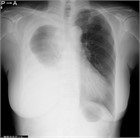

1. がん性胸膜炎に対する胸膜癒着療法のランダム化第3相試験:滅菌調整タルクvs. OK-432(WJOG8415L、J-PLEURA)の結果が世界肺癌学会(WCLC)2024で報告された。主要評価項目は胸膜癒着術30日後の胸水無再発割合であり、OK-432 43.9%、滅菌調整タルク 29.6% (p=0.9965)と有意差は認めなかった。

1. 癌性胸膜炎の症例に対する胸膜癒着術に使用する薬剤は、タルクが勧められる(推奨度1)

1. タルクの投与法としては、poudrageが推奨される(推奨度1)

1. ピシバニール等も使用されることがあるが、タルク以外の癒着剤の効果は同等である(推奨度2)